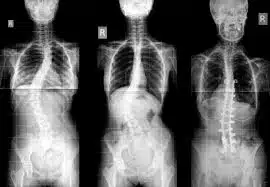

Scoliosis means that the spine in the back does not run straight and curves to the side. The angle of the curve may be small, mild or large, but it is considered scoliosis if it measures more than 10 degrees. The greater the angle of the spine curve, the more likely it is to develop over time. You may not easily diagnose this problem by looking directly at someone’s spine, but you may notice it when she/he stands. Because it causes the patient to lean a little or have uneven shoulders or hips.

When the scoliosis degree hits 40 or 50, surgery is recommended by doctors. This is true for both teens and adults. In the teen’s signs of the curve, the increase has to be present, as well. In adults, surgical treatment is recommended when the degree of the curve is 50 and the patient has nerve damage to legs or bowl or causes bladder problems. The goal of scoliosis surgery is to straighten the curve and avoid it from progressing in the future. Metal implants and rods are put in the spine to reduce or eliminate the curves. Also, the surgery keeps the spine curve straight until fusion occurs. Fusion is the knitting together of the spinal element.